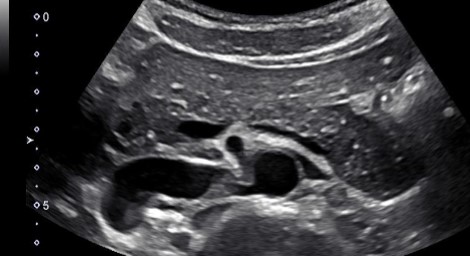

This image was taken in what plane?

Explain your answer.

Transverse

The entire pancreas is visualized